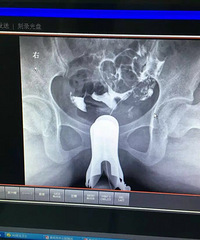

做了输卵管造影检查 医生只给开了一大堆药 有懂的人吗?